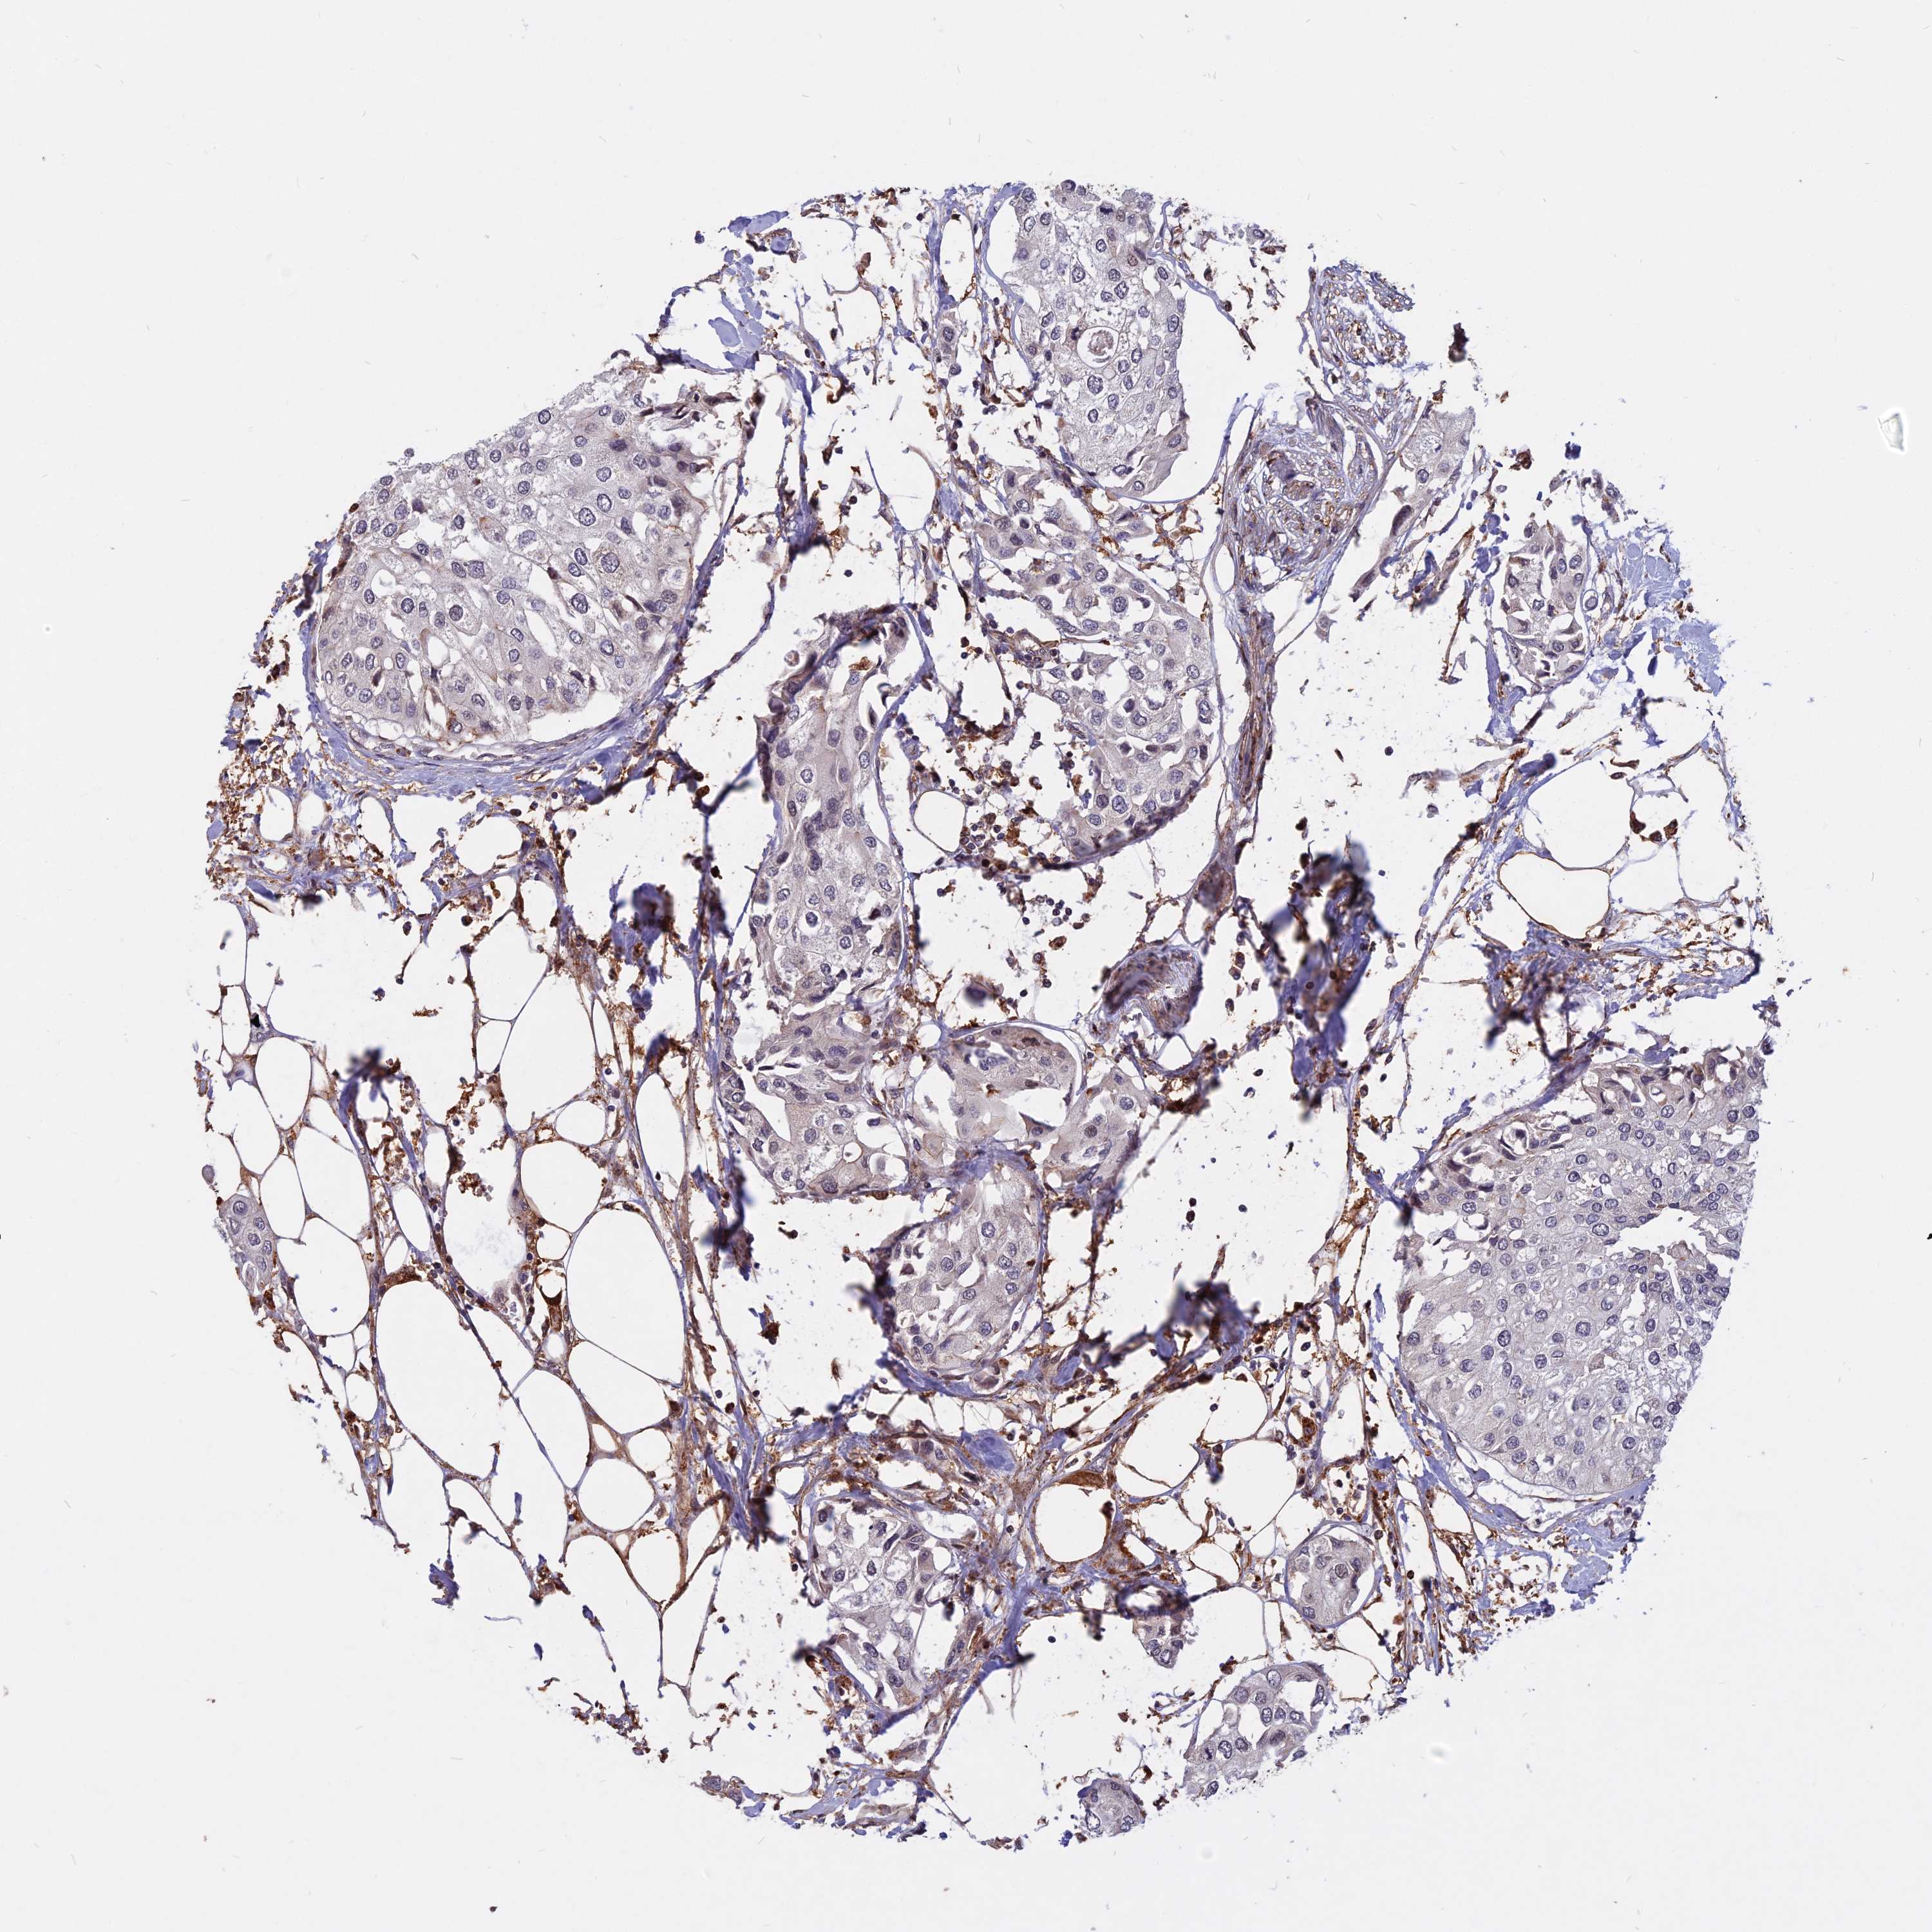

UROTHELIAL CANCER - Protein expressioni

A mouse-over function shows sample information and annotation data. Click on an image to view it in a full screen mode. Samples can be filtered based on level of antibody staining by selecting one or several of the following categories: high, medium, low and not detected. The assay and annotation is described here.

Note that samples used for immunohistochemistry by the Human Protein Atlas do not correspond to samples in the TCGA dataset.

Antibody stainingi

Antibody staining in the annotated cell types in the current human tissue is reported as not detected, low, medium, or high, based on conventional immunohistochemistry profiling in selected tissues. This score is based on the combination of the staining intensity and fraction of stained cells.

Each image is clickable and will lead to virtual microscopy that enables deeper exploration of all samples and also displays staining intensity scores, fraction scores and subcellular localization as well as patient and tissue information for each sample.

Antibody HPA040412

Antibody HPA040947

Urothelial carcinoma, High grade

Urothelial carcinoma, Low grade